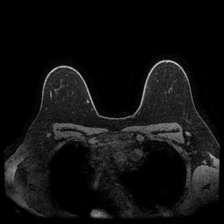

DUKE Breast Cancer Dataset – This dataset, obtained from 922 patients with invasive breast cancers collected at Duke Hospital over 14 years, is one of the largest publicly available breast cancer 3D MRI image datasets, where the task is identifying the presence of breast tumors [23].

Using the trained models with state-of-the-art performance, we follow the protocol detailed in Section 2.4 and present experimental results on interpretability in Figure 3, Figure 4, and Table 3. In particular, Figure 3 illustrates several qualitative examples, while Table 3 displays pointing game accuracy and mean IoU scores. Finally, Figure 4 represents IoU distributions represented in the form of boxplots. Based on these results, we make the observations below.

Qualitative results can be misleading. In Figure 3, we present qualitative interpretability outputs for all methods considered. As can be seen, depending on the selected subset of images and the method, both accurate and inaccurate interpretability maps can be found. These findings emphasize the danger of making strong claims about interpretability methods based solely on qualitative results, including attention maps.